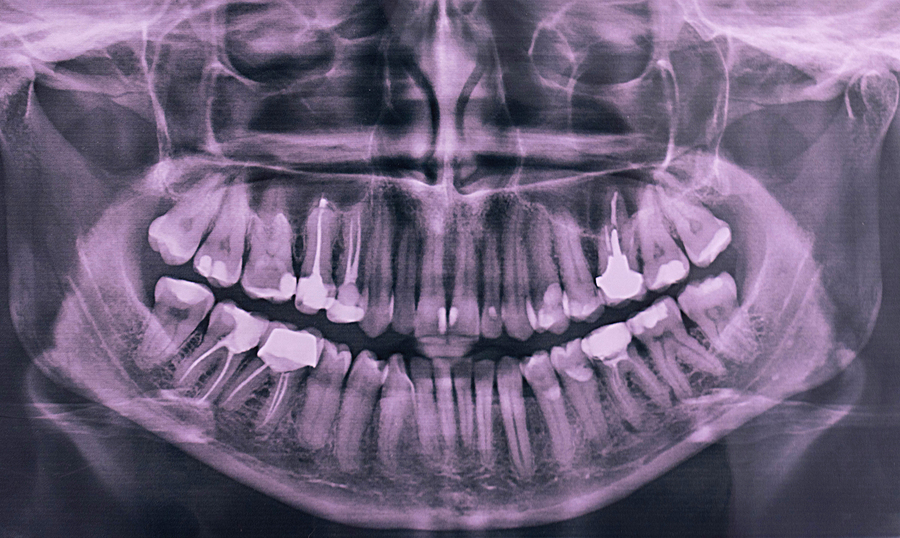

They are made by a panoramic X-ray machine that rotates around your head. The panoramic X-ray is commonly used to detect wisdom teeth; acquire more information about jaw issues and missing or extra teeth; help identify abscesses, cysts, and tumors; and evaluate growth and development in children. This type of X-ray also provides information.

What is Panoramic X-ray? Panoramic radiography, also called panoramic x-ray, is a two-dimensional (2-D) dental x-ray examination that captures the entire mouth in a single image, including the teeth, upper and lower jaws, surrounding structures and tissues.. The jaw is a curved structure similar to that of a horseshoe. However, the panoramic x-ray produces a flat image of the curved structure.

Panoramic: large single x-ray that shows all the teeth and the jaw bone. This kind of x-ray is used a lot in orthodontics, and in evaluating missing teeth, extra teeth and wisdom teeth. Cone Beam CT: large single x-ray that shows a 3D image of the desired area. These CT scans do produce a little more radiation than the x-rays.

Some of the things your dentist will examine in your dental X-rays include: Position, size, and number of teeth. Changes in the root canal. Bone loss in the jaw or facial bones. Bone fractures. Tooth decay, including between teeth or under fillings. Abscesses and cysts.

A panoramic dental x-ray captures a single image that shows your teeth, jawbones and surrounding facial structures. Dentists and oral surgeons use these x-rays to diagnose dental problems and plan treatments, especially for restorative dentistry like dental implants, or teeth straightening and orthodontic work.. Here you can discover how panoramic radiography works, what to expect from the.